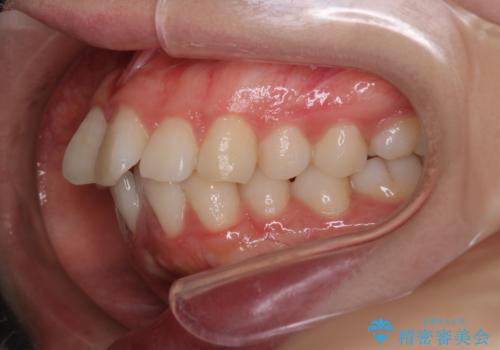

【抜歯インビザ】凸凹を綺麗になおしたい

- 前歯の凸凹を主訴に来院されました。

叢生量が多いため、抜歯が必要となるため、ワイヤー矯正をお勧めしましたが、患者さんの希望によりインビザラインで治療を開始しました。途中でワイヤーリカバリーを必要とせず終了でき患者さんには満足していただけました。